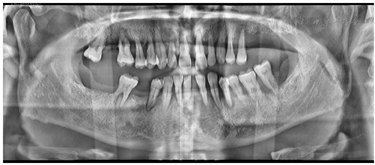

17、25、26、27、28、31、34、37、38、45、47、48缺失,缺牙区牙槽嵴低平。25、34、37拔牙创处于愈合期。口腔卫生情况欠佳,探诊深度PD 4-11mm,附着丧失1~10 mm,牙龈暗红,质地疏松,探诊出血,BOP%=100%,可探及连续龈下结石。18、16、11、21、32、33、35、36、41、42、43、44、46松动III度,15、14、13、12、22、23、24松动II度。前牙深覆牙合,右侧后牙咬合中性关系(图1)。颞下颌关节检查未见异常。影像学检查:初诊全景片显示余留牙牙槽骨水平性吸收至根尖1/3(图2)。术前CBCT截图显示15、14、13、12、22、23、24牙槽骨吸收至根中1/3水平,其余牙牙槽骨吸收至根尖1/3不等(图3)。

术后复查:术后3月全景片显示种植体骨结合良好(图7)。制作终义齿:术后5月:取下临时固定义齿,制取上下颌硅橡胶印模,根据临时义齿,记录上下颌颌位关系,上牙合架。术后6个月:制作义齿蜡型、排牙(图8),取下临时固定义齿,口内试戴上下颌终义齿蜡型,检查咬合关系良好,上下颌中线居中、对称,露齿线、唇颊面部丰满度患者满意。术后6个月:取下临时义齿,戴入终义齿,修复至第一磨牙(图9)。随访术后1年:全景片显示种植体周围骨结合良好,上前牙区种植体颈部骨吸收约1 mm(图10)。术后2年:义齿外形无变化,组织面有菌斑沉积。治疗计划:1.患者口腔卫生宣教,指导正确刷牙,采用冲牙器冲洗义齿与牙龈间缝隙,要求定期(6个月)复查、维护。2.取下上下颌义齿,复合基台周围洁治,清洁义齿,抛光义齿组织面,重新戴入固定上下颌义齿(图11)。术后2年全景片:种植修复前后面像对比(图13)。